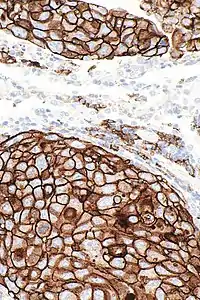

Micrograph showing a PD-L1 positive lung adenocarcinoma. PD-L1 immunostain.

PD-L1 is shown to be highly expressed in a variety of malignancies, particularly lung cancer. In order to anticipate the effectiveness of gene therapy or systemic immunotherapy in blocking the PD-1 and PD-L1 checkpoints, PD-L1 might be employed as a prognostic marker and a target for anti-cancer immunity.[22] i.e. upregulation of PD-L1 may allow cancers to evade the host immune system. For example, an analysis of 196 tumor specimens from patients with renal cell carcinoma found that high tumor expression of PD-L1 was associated with increased tumor aggressiveness and a 4.5-fold increased risk of death.[23]